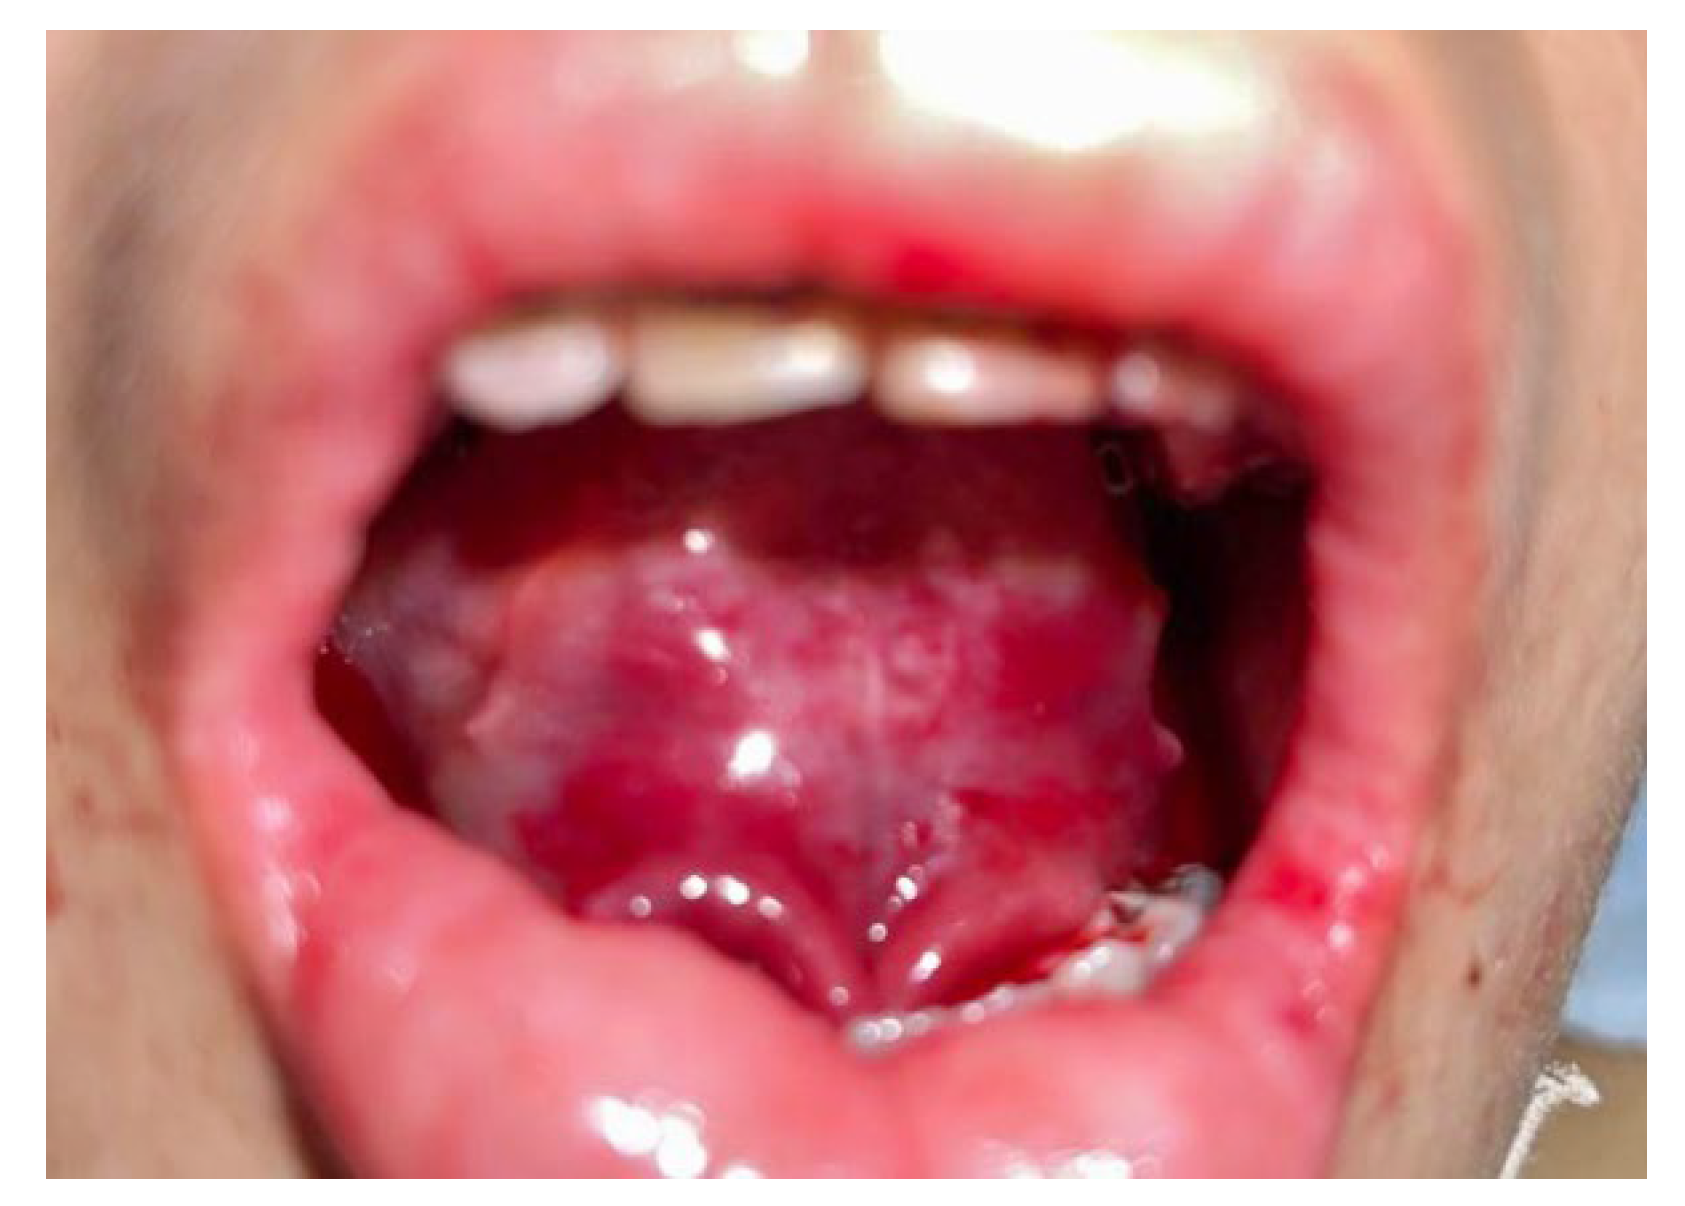

2. Case Report